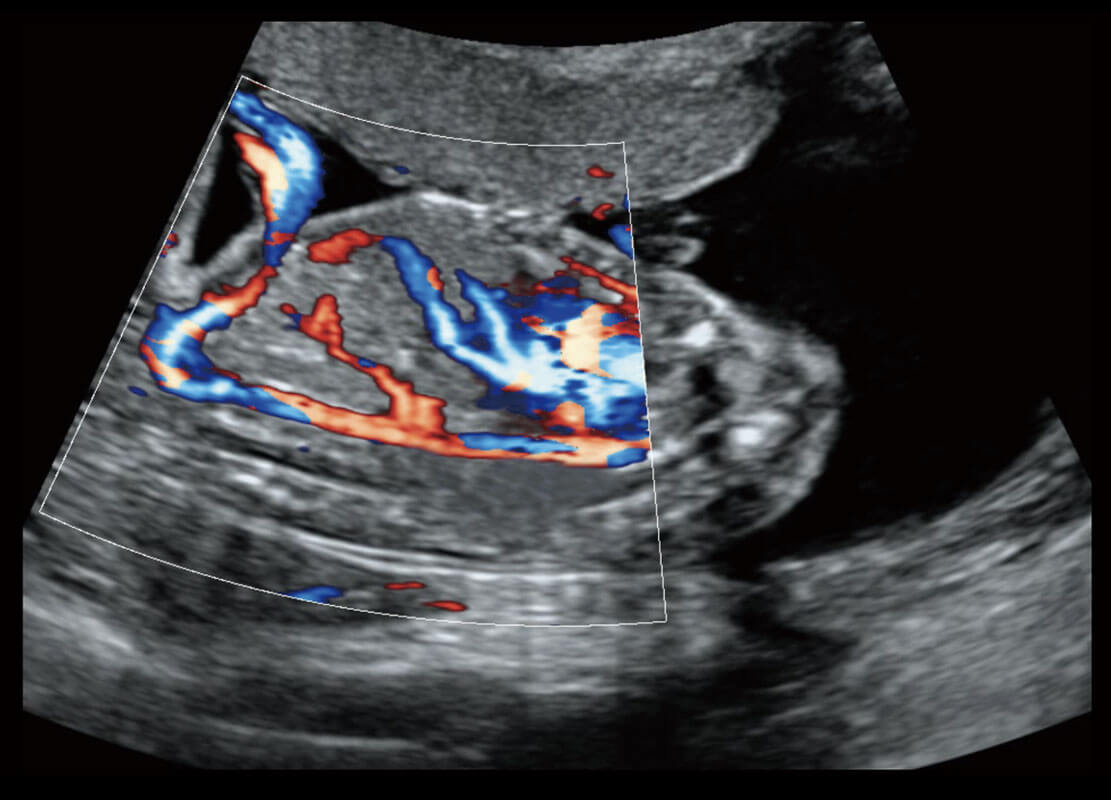

• 胎儿体循环

• 四腔心血流